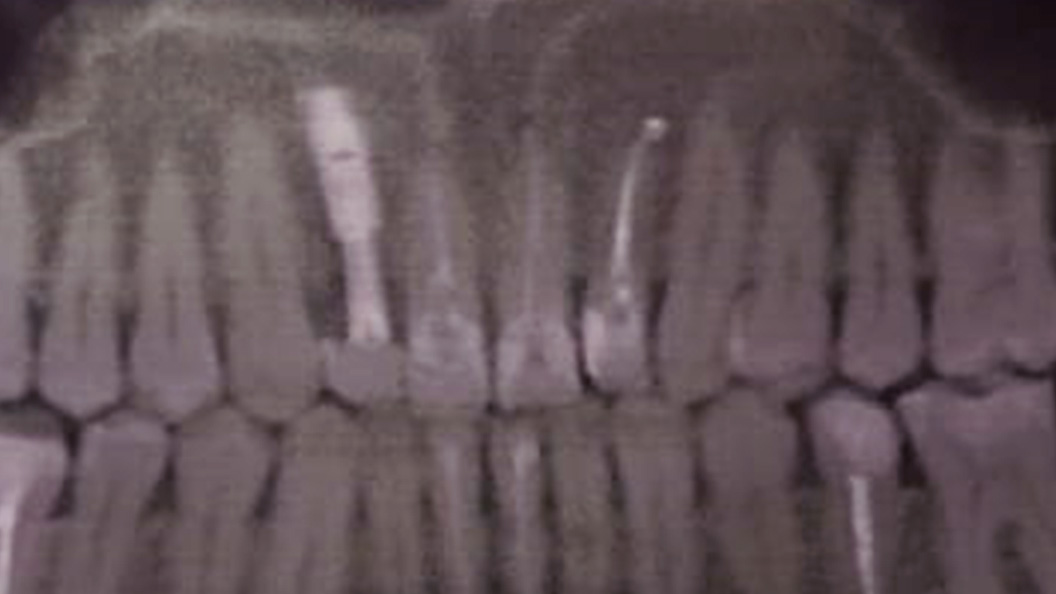

До и после лечения

Пациентка обратилась в «Стоматологию Комфорта» с жалобами на периодические ноющие боли в зубе 1.2. Врач Тарасов Денис Геннадьевич провёл обследование и поставил диагноз — хронический периодонтит верхнего резца. Проведено удаление зуба с одномоментной имплантацией.

- проведение одномоментной имплантации;

- установка коронки.